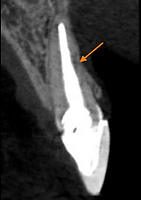

Realizamos então a exodontia do incisivo central superior direito, seguido de implante, enxerto 100% com biomaterial, provisório imediato e posterior troca da faceta do incisivo central superior esquerdo. A maior preocupação era utilizar uma técnica cirúrgica que mantivesse o alinhamento da gengiva com os dentes vizinhos e uma reabilitação protética que escondesse o implante e a faceta do dente vizinho no conjunto do sorriso.